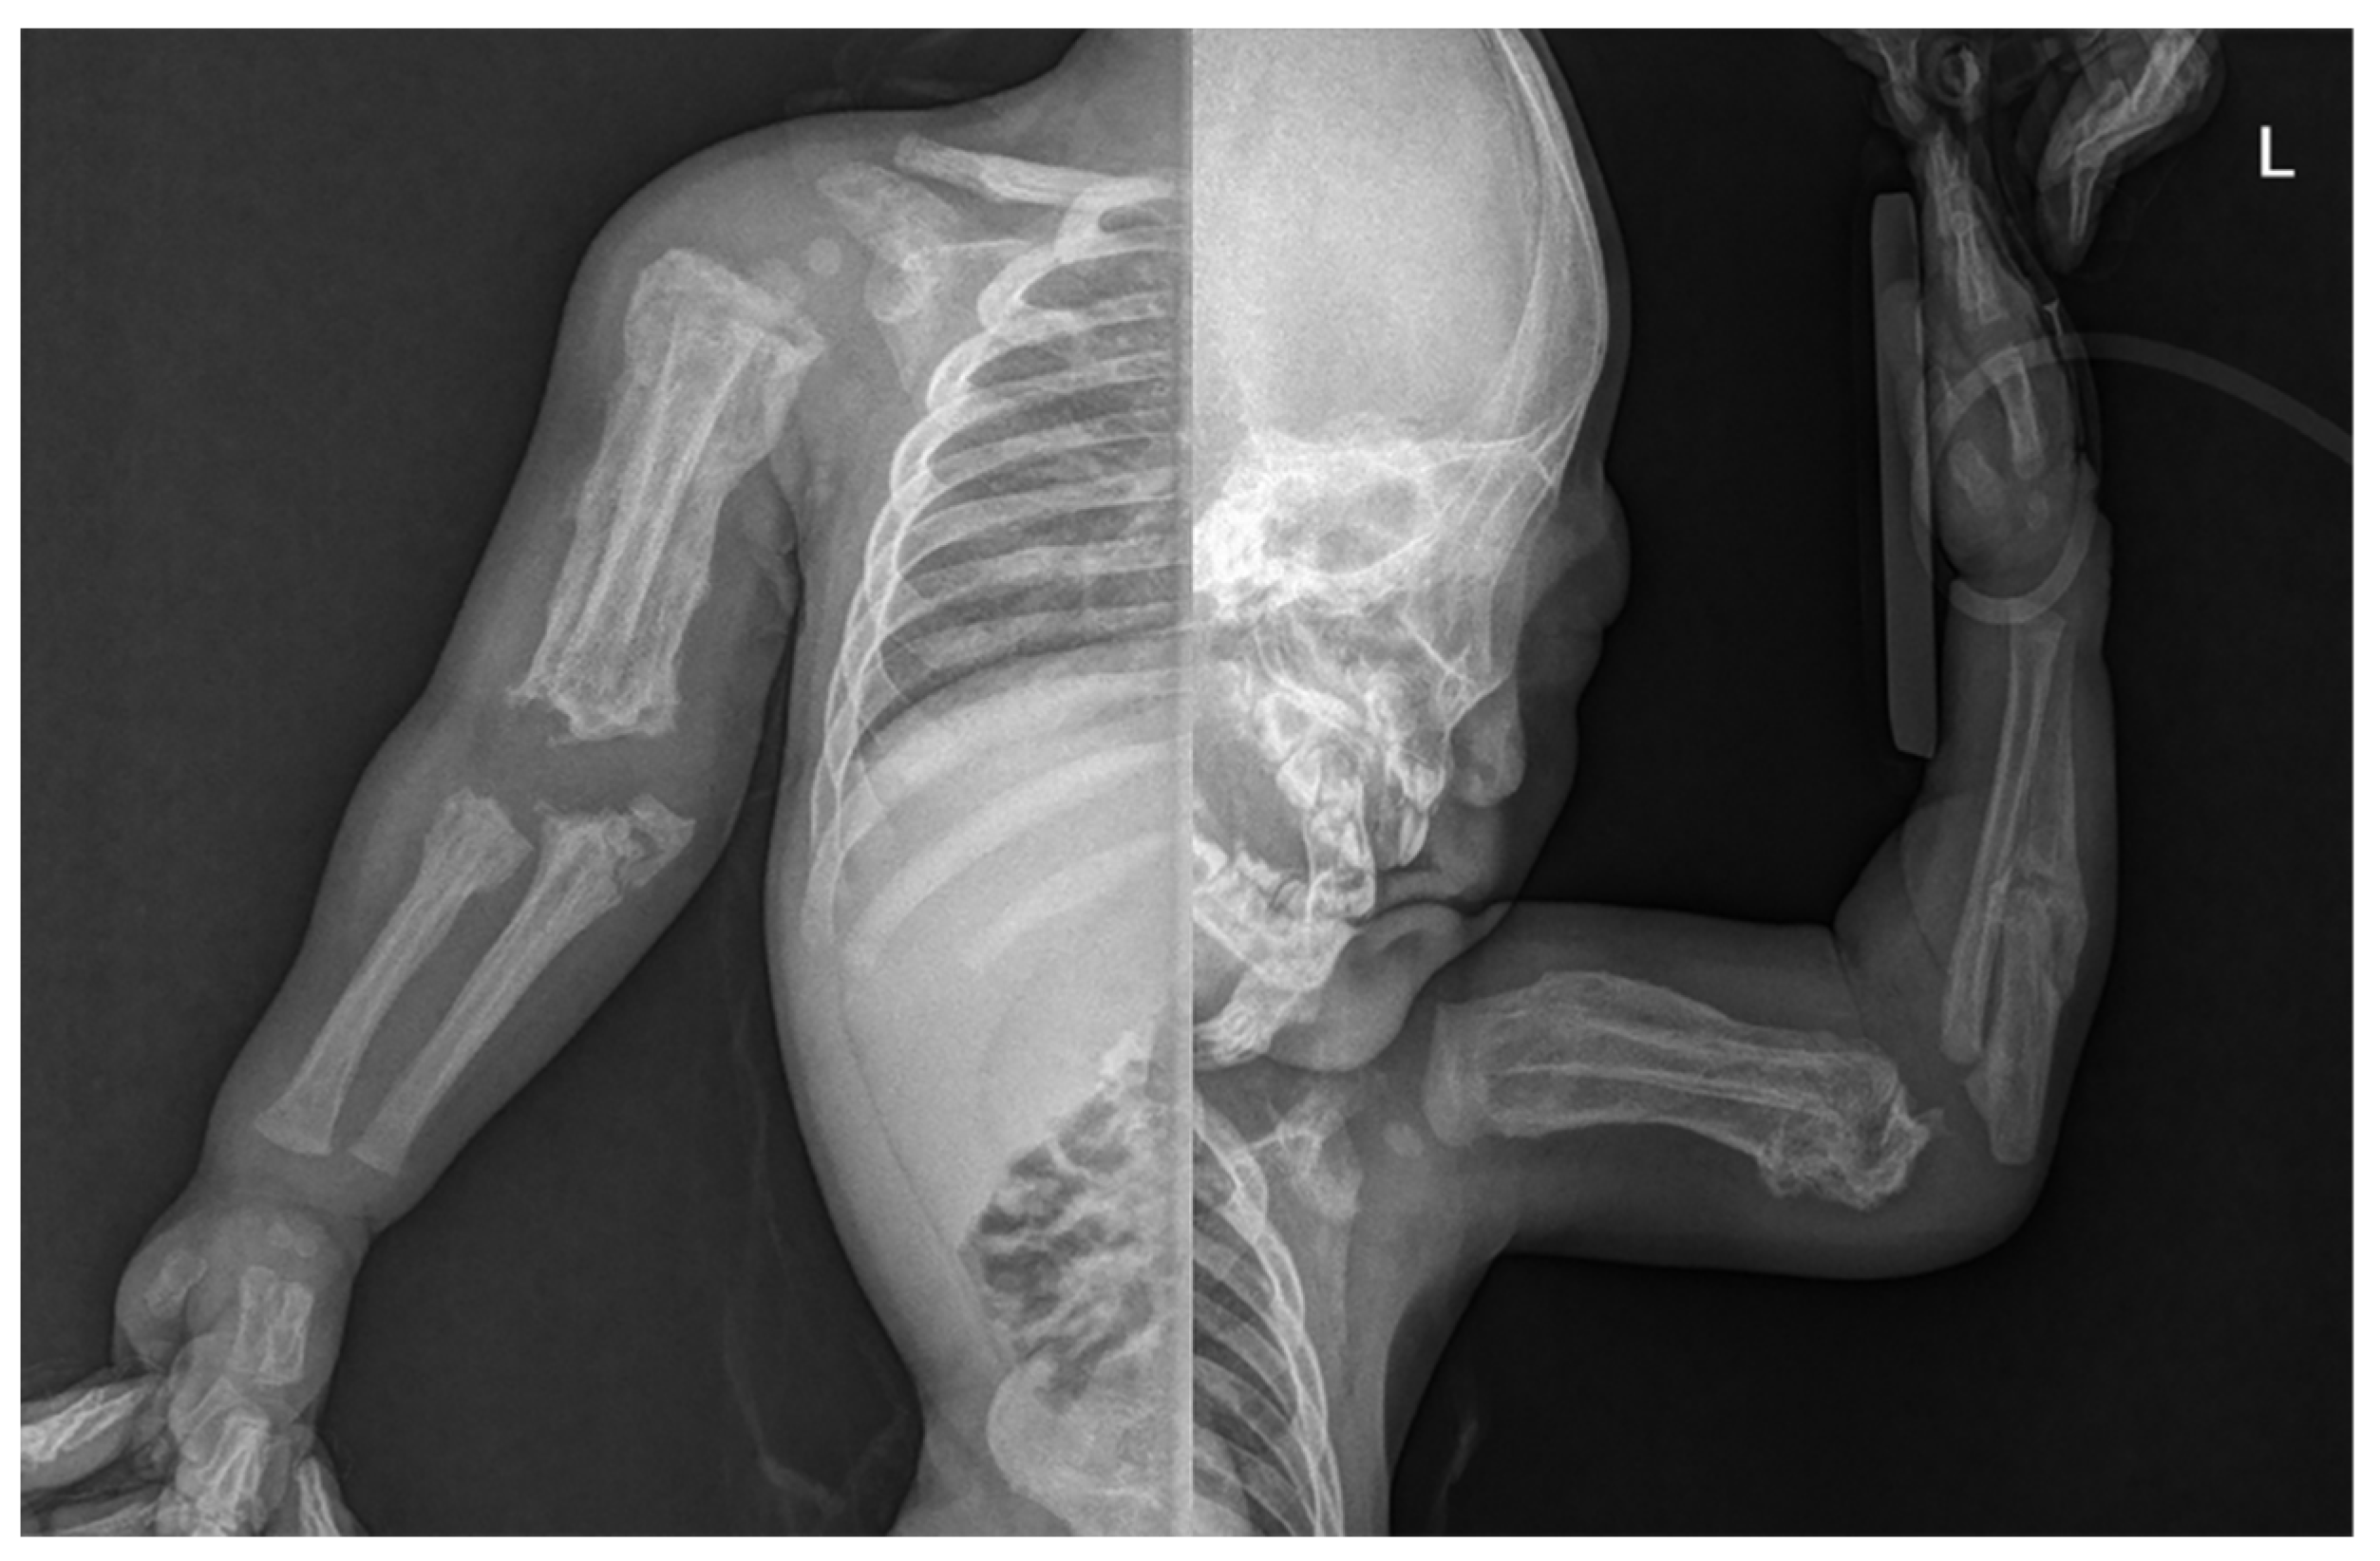

Skin lesions such as bruises or abrasions were not observed in the extremities, but an extensive periosteal reaction with transverse fractures was observed in both upper and lower long bones (Figure 2). There was no specific history of injury. Radiographs showed multiple fractures of both femurs, right tibia, and both ulna in various stages of healing. Spiral fractures were observed in the right tibia and right ulna (Figure 3).

Figure 3. Radiograph of upper limb showing hyperostosis with fractures of both ulna.